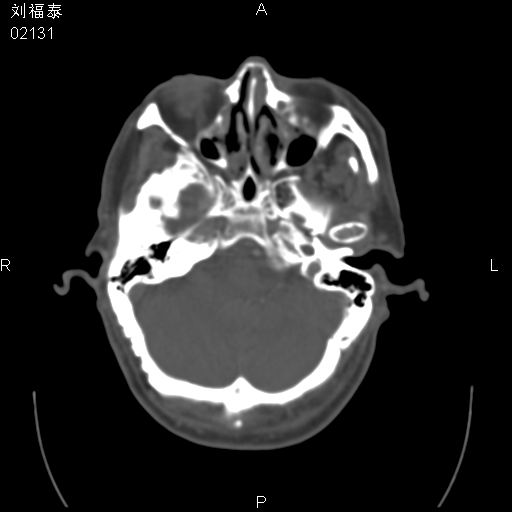

以下是引用余辉在2008-3-4 14:00:00的发言:[br]考虑左眼球黑色素瘤或血管源性肿瘤可能性大,建议增强检查

以下是引用余辉在2008-3-4 14:00:00的发言:[br]考虑眼球黑色素瘤或血管源性肿瘤可能性大,建议增强检查

以下是引用zsl6918在2008-3-4 15:08:00的发言:[br]现有征象只能提示球内出血,视网膜脱落,至于是否为肿瘤性病变需mri检查。